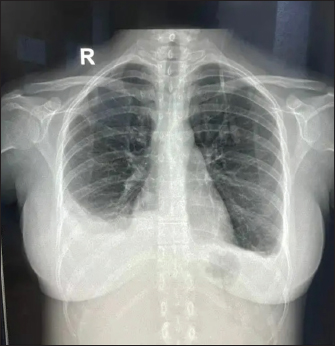

USG’s whole abdomen revealed hepatomegaly and mild to moderate ascites. In view of melena and thrombocytopenia, 6 units of random donor platelets were transfused. A workup for fever with thrombocytopenia and polyserositis was started. Dengue RTPCR, NS1 antigen, IgM, Weil felix, and VDRL were negative. Viral markers (HIV/HBsAg/Anti HCV/Anti HAV IgM/Anti HEV IgM) were negative. Scrub IgM, Brucella IgM, Urinary legionella antigen, CMV PCR, and Leptospira IgM were negative. Malaria Ag and P/S for the malaria parasite were negative. The widal test and Typhidot IgM were negative. CPK and CK-MB were negative. Stool occult blood (three samples) were negative. Covid PCR was negative. Blood and urine C/S were negative. Urine KOH revealed few budding yeast cells. Urine fungal culture was negative. Workup for EBV revealed 24,300 copies of EBV RTPCR and EBV IgM and IgG were positive. We did an autoimmune workup considering a young female with polyserositis but both ANA by Immunofluorescence and ANA profile were negative. Direct and indirect Coombs tests were negative. By the end of first week of admission, thrombocytopenia started improving but she had a persistent cough and fever although spikes were reduced. A 2D echo revealed trace pericardial effusion. Repeat Chest X-ray revealed persistent bilateral pleural effusion (Right > Left) (Fig. 2). In view of persistent effusion, we decided to perform a CECT chest and abdomen which revealed evidence of moderate right pleural effusion, minimal fluid in the left pleural cavity with atelectatic changes in the adjacent lung, oedematous thickened gallbladder and mild ascites (Figs. 3 and 4).

Fig. 2. Repeat chest X-ray showing persistent bilateral pleural effusion (Right > Left).